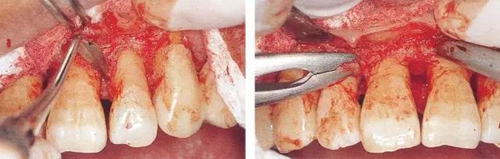

▼圖14-1(左)  用牙齦刀(ARUBA翻瓣器)將牙間部的牙間水平纖維以及牙槽嵴頂纖維切斷。

▼圖14-2(右)  將完全切割分離的組織用牙齦鉗將整塊比較容易的去除。

13.jpg

▼圖14-3  根面和骨面殘存的小肉芽組織,利用刮匙完全去除。炎癥性肉芽組織如果能去除,出血就會變少,清創(chuàng)處理會容易進行。

14.jpg